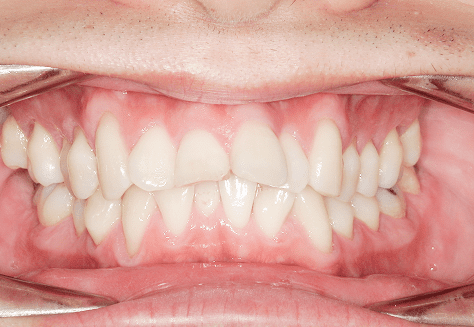

M.U

治療前

治療後

主訴

下の歯が特にガタガタなのが気になる。上の前歯が1本反対になっている。

診断

下顎前突・叢生・反対咬合

年齢/性別

20代/男性

抜歯部位

非抜歯

使用装置

上下インビザライン(PBM使用)

保定装置

ビベラリテーナー

料金

初回資料採得・・・・・・・30,000円

診断料・・・・・・・・・・33,000円

動的治療終了時資料採得・・5,500円 -

基本料金

950,000円

診察料金

5,500円×16回

治療期間

1年7カ月